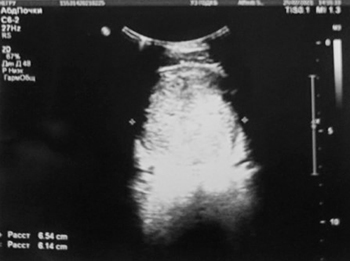

МРТ таза: новообразование больших размеров. МР-картина больше в пользу рабдомиосаркомы, исходящей из предстательной железы с инвазией мочевого пузыря.

Вторичный двусторонний уретерогидронефроз. Состояние после цистостомии (см. рис. 3).

Рисунок 3. Результаты МРТ таза.